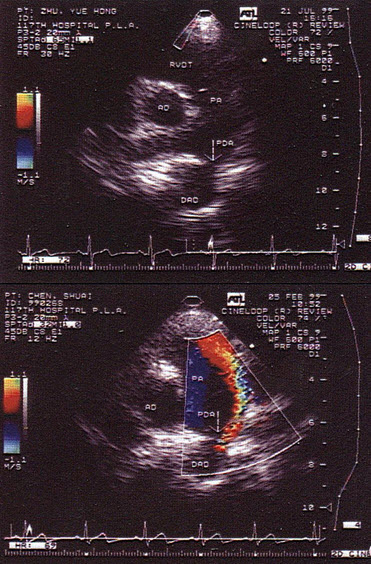

14、单项选择题

如图,最可能的诊断是()